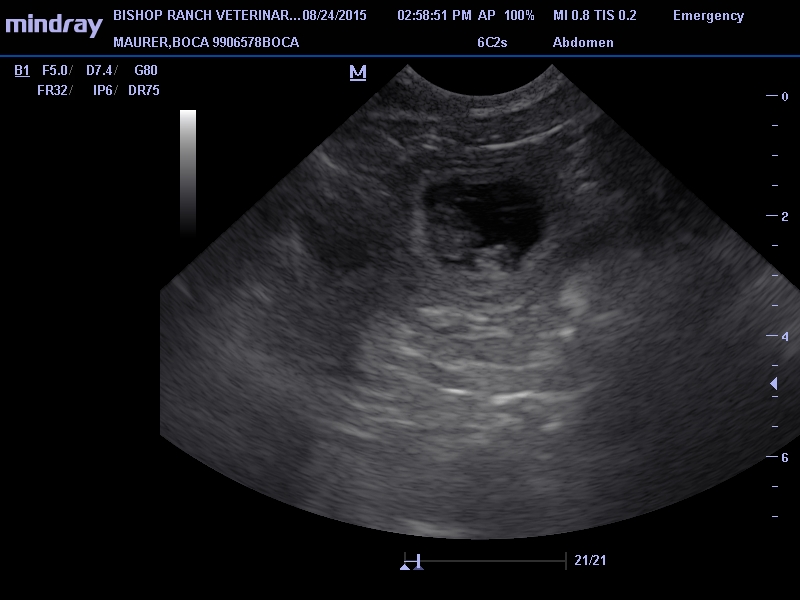

Boca is pregnant!

We took Boca in to Bishop Ranch Veterinary Center today for her ultrasound with Dr Cain and Boca is definitely pregnant!  There are maybe 7-8 pups in there, and all looked good according to the doc.  Due date is September 25, 2015.